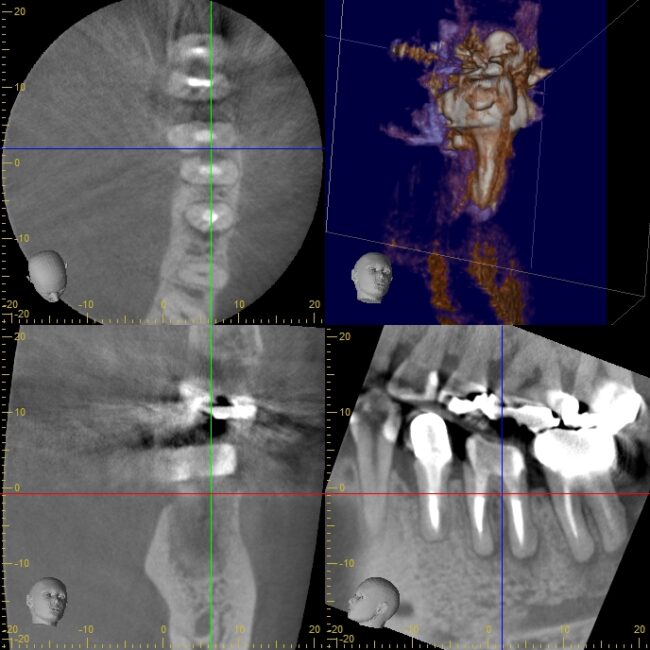

術前3DCT

このような、厚い皮質骨(骨の表面の硬い部分)に取り囲まれた病変は、通常のデンタルX線では発見することが困難なこともありますが、歯科用3DCTだと、病変の有無、位置や大きさを把握することが可能になります。

術前の状況を正確に診断することは非常に大事なことです。

また、術前のCTによって、治療の予後を正確に評価することができます。